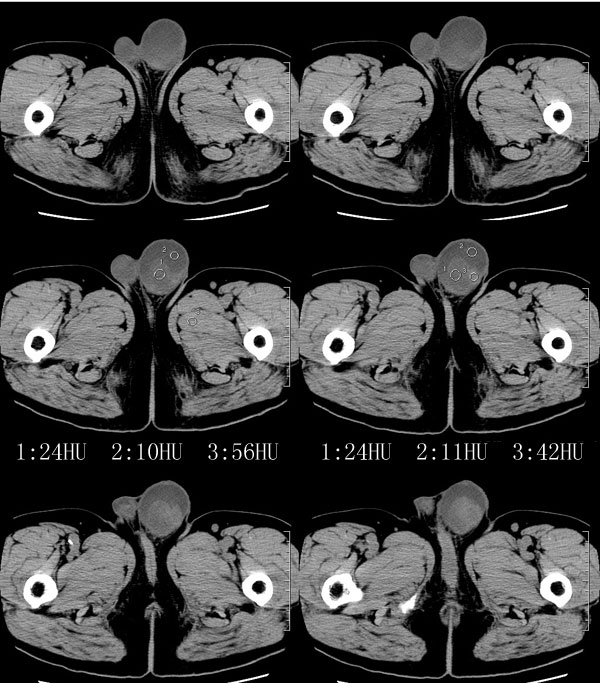

| 男性,69岁。自2个月前开始无意中发现左侧阴囊内一鸡蛋大小肿物,当时无伴疼痛等不适,未予重视。肿物逐渐增大,近段时间常伴左会阴部、腹股沟区牵扯不适,并于2周前在我院门诊行彩超检查提示“左侧附睾肿瘤可能,左侧睾丸鞘膜积液”。 专科检查:左侧阴囊肿大,其内可触及一鹅蛋大小肿物,表面光滑。肿物前部呈囊性感,后部质硬,按压无疼痛,无缩小,活动度良好。左侧睾丸未触及,透光试验(±)。                 王仕学发言:左侧睾丸见一密度不均肿块,边缘清楚,周围见水样密度影;考虑睾丸生殖细胞性肿瘤可能性大. 睾丸肿瘤占生殖系统肿瘤的3%-5%,占男性恶性肿瘤的0.5%-1.0%,其中生殖细胞性肿瘤占95%.睾丸肿瘤包括生殖细胞和非生殖细胞肿瘤两大类,前者占95%以上,后者不到5%.非生殖细胞肿瘤虽少见,但种类繁杂,主要有支持细胞、间质细胞和支持细胞-间质细胞瘤等功能性肿瘤,和间皮瘤、腺癌、横纹肌肉瘤、粘液性囊腺瘤、纤维上皮瘤、黑素神经外胚瘤、淋巴瘤等附属组织肿瘤。不同的病理类型的睾丸肿瘤发病率高峰不同,睾丸癌多发于35岁以前,精原细胞瘤发病高峰为30-35岁。精原细胞瘤约占睾丸肿瘤的60%,发病高峰在30-35岁。85%的患者睾丸有明显肿大,肿瘤局部侵犯力较低,肿瘤一般有明显界限。 手术:行“左侧附睾、睾丸、精索切除术”。 病理诊断:(左睾丸、附睾)肿物,为低分化腺癌。另送检(左精索远端)肿物,镜下亦为低分化腺癌。 免疫组化:ck(l)(++++)、cea(+++)、ca19-9(-)、psa(-)、plap(-)、p53(-)、vimentin(-)。 原贴地址:http://www.radinet.com.cn/forum_view.asp?forum_id=4&view_id=30707 |